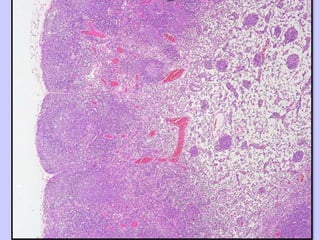

Divisiones del ganglio

linfático

• Corteza:

– Externa, mayor cantidad de linfocitos,

fuertemente teñida

• Médula:

– Interna, más pálida . Vasos linfáticos y senos

medulares ocupados por linfocitos, macrófagos y

células plasmáticas

• Estroma:

– Red de fibras reticulares y células reticulares

CORTEZA

• Masa densa de

células linfoides, a

veces atravesada

por trabéculas y

senos

intermedios.

• Presenta los

nódulos linfoides

primarios,

secundarios y

tejido linfoide

difuso.

MEDULA

• Se encuentran los

Cordones Medulares:

– Agregaciones de tejido

linfoide organizadas

entorno a vasos sanguíneos

pequeños.

• Los cordones se

ramifican, anastomosan y

terminan a nivel del hilio.

• Están formados de

linfocitos pequeños,

células plasmáticas y

macrófagos